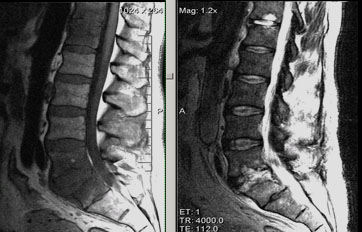

- в некоторых случаях для уточнения локализации и детальной картины патологии – МРТ или КТ;

- Рентгенографию (возможно, контрастную)

- При необходимости, более точное исследование при помощи КТ и МРТ